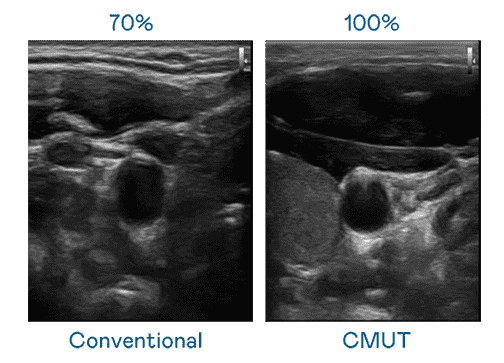

CMUT 技术是一种用电容式微机电元件来产生超音波讯号的技术。。与传统 PZT 压电式技术相比,,CMUT 频宽增加 30%,,,更宽频的超音波讯号让影像解析度大幅提升,,是实现高影像品质医疗超音波扫描、、、促进精准医疗发展的关键技术。。

大频宽带来超清晰影像

超音波影像的解析度高低,,,,首先取决于探头能发出的讯号频宽。。。尊龙z6 CMUT 可提供高清晰的超音波讯号,,提供高频宽、、、、高灵敏度、、、、影像纹理细节更高的超音波影像,,,协助医护人员缩短影像判读时间及利用精准的医疗影像进行诊断。。。